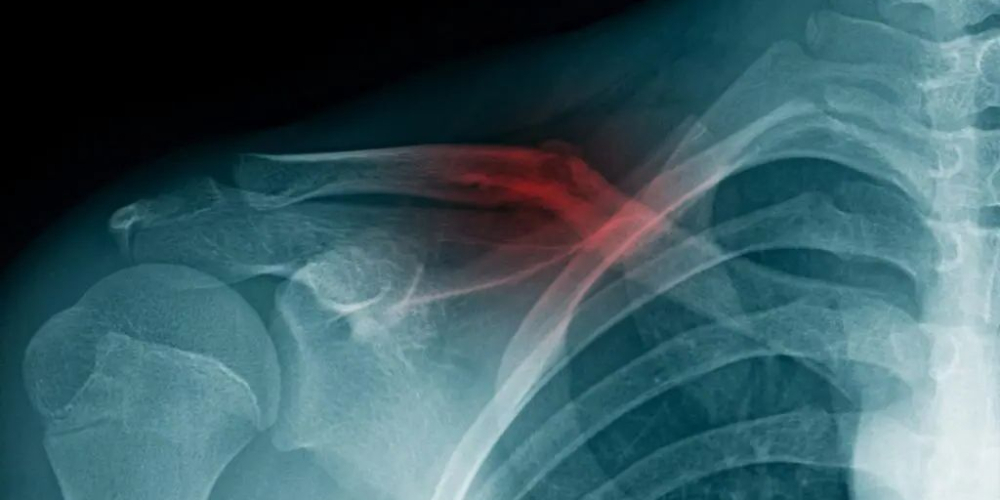

Перелом ключицы

Перелом ключицы — это повреждение кости, которая соединяет грудину с лопаткой и укрепляет плечевой пояс. Травма вызывает сильную боль и неспособность полноценно двигать рукой.

Как правило, после проведения визуального осмотра диагноз не вызывает сомнений. Однако для получения точной информации о характере травмы и выборе лечебной тактики необходимо пройти рентгенологическое обследование, которое считается «золотым стандартом» в диагностике перелома ключицы. В некоторых случаях для исключения возможного повреждения мягких тканей может быть назначено КТ или МРТ.